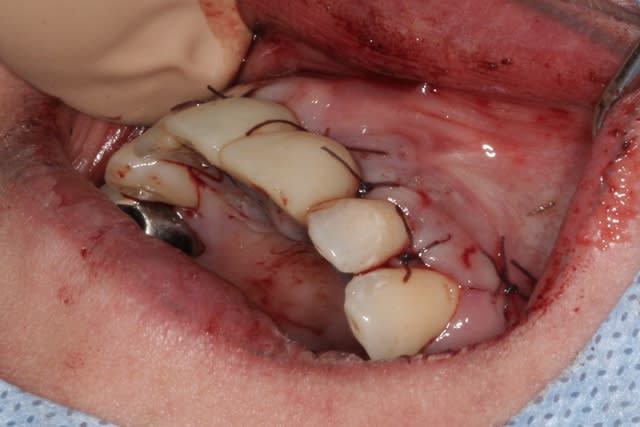

tien, ce matin, extraction de 24/25, curetage méticuleux, forage, comblement du gap, pose des 2 implants qui se sont bloqués à 50Ncm au CA sur les 3 ou 4 mm apicaux, pose des vis de cicat, sutures...35min....tranquille...

un autre cas EII MCI sur 11/21...mais en photos (j'ai aussi la vidéo, faut que je la passe sur youtube)

par contre il faut veiller à avoir une bonne étanchéité au niveau des sutures...